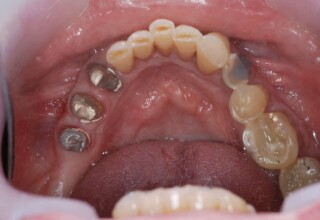

Extensive case with crowns in almost all teeth

Extensive case with crowns in almost all teeth due to extensive wear, old restorations, posterior root canals and aesthetic concerns. Patient (60years old) presented with intense bruxism which he never had treated. Consequently, he obtained very deep cervical abrasions which jeopardized tooth integrity. Restorations (fillings) were executed mainly with adhesive resinous materials and three custom cast post and cores. Temporary crowns were placed to evaluate the desired size, shape and position of the teeth before permanent crown fabrication.